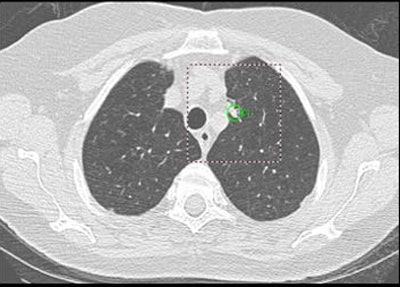

| Above: A 7-mm nodule in right middle lobe, representing a true-positive CAD finding. Below: A 5-mm nodule in the lower right lobe, representing a true-positive CAD finding. |